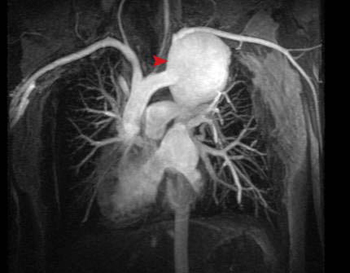

Above is a coronal MRA that shows a large thoracic aortic arch fusiform aneurysm in the vicinity of the subclavian artery. The aneurysm was larger than 5.5 cm, so surgical intervention was necessary.